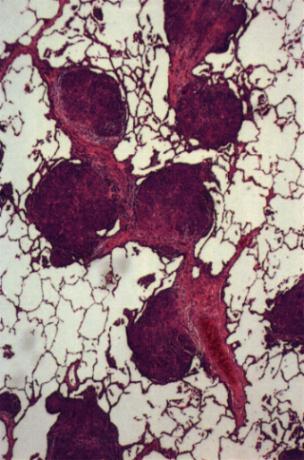

En las enfermedades intersticiales del pulmón predomina la inflamación crónica y reparación celular con fibrosis. La inflamación crónica es en algunas enfermedades de tipo granulomatosa En la siguiente figura se observa un esquema de la patogénesis de estas enfermedades donde se destaca al macrófago como la célula principal (x). El macrófago, como célula fundamental de los procesos inflamatorios crónicos libera mediadores químicos que producen daños celular o mediadores que estimulan la fibrosis (x). En territorio intraalveolar esto se manifiesta en hiperplasia e hipertrofia de los neumocitos tipo II, como se observa en el siguiente esquema (x) y la siguiente microfotografía donde se observa un alvéolo con hiperplasia de los neumocitos tipo II (x). La hiperplasia de los neumocitos tipo II es un fenómeno reactivo y no central en la enfermedad. El proceso central de la enfermedad ocurre en el intersticio donde el macrófago, probablemente, por la incapacidad de eliminar el agente causal de estas enfermedades se agrupa dando origen a las células gigantes multinucleadas y a los granulomas (inflamación crónica granulomatosa) como se ve en las dos siguientes microfotografías con alto aumento (40x) y bajo aumento (4x). Ambas son imágenes características de la sarcoidosis, un tipo de enfermedad restrictiva. Estos granulomas, pueden permanecer como lesiones inflamatorias (por ej. Sarcoidosis, Beriliosis) o ir rápidamente a la fibrosis, En la siguiente imagen se observa un nódulo de fibrosis intersticial característico de Silicosis pulmonar (x). En algunas enfermedades intersticiales predomina directamente la activación de fibroblastos, sin pasar por la etapa de inflamación granulomatosa crónica. En estos casos va a predominar la fibrosis difusa, característico de la Asbestosis (x). Una clasificación de las enfermedades intersticiales más representativas se muestra en la tabla 1 (x).